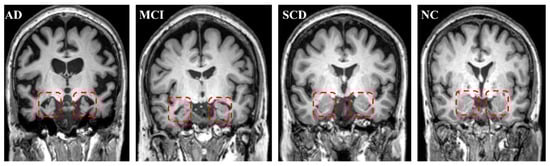

3.2. AD vs. NC

AD showed a significant, whole GM volume (GMV) reduction compared with NCs (p < 0.001). For the WM volume (WMV) and total intracranial volume (TIV), AD did not display a significant decrease compared with NCs (Table 2). However, volume measurements showed a significant decline in the AD group on both the left and right hippocampus compared with those in the NC group (p < 0.001 for both sides). The total hippocampus volume also significantly decreased compared with NCs (Table 2 and Figure 4). Figure 5 displays the bilateral hippocampal volume of typical AD, MCI, SCD, and NC subjects. AD showed the most apparent bilateral hippocampal volume reduction. AD also exhibited a significant decrease in the bilateral hippocampus MK and an increase in MD compared with those in NC, respectively (Table 2 and Figure 4). The right hippocampus volume showed a pronounced percentage change in the AD group (Table 3). In the ROC analysis, the right hippocampal volume showed the most prominent area under the curve value (AUC = 0.977) (Table 4 and Figure 6).

Figure 5.

Typical subjects for AD, MCI, SCD, and NCs. The red square contains the bilateral hippocampus. The atrophy of the bilateral hippocampus for AD is the most severe; MCI is intermediate. There was no hippocampal atrophy for SCD compared with NCs.